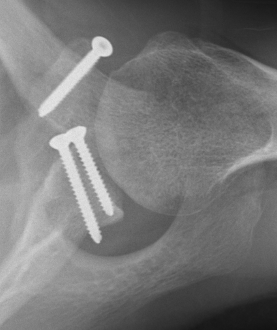

Case 1

- > 1 cm medial displacement

- ORIF via posterior / modified Judet approach